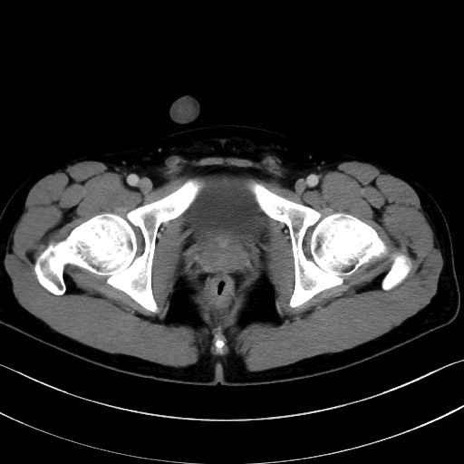

4. 深層外旋六筋(股関節の深部)

内閉鎖筋 (Obturator internus)

外閉鎖筋 (Obturator externus)

大腿方形筋 (Quadratus femoris)